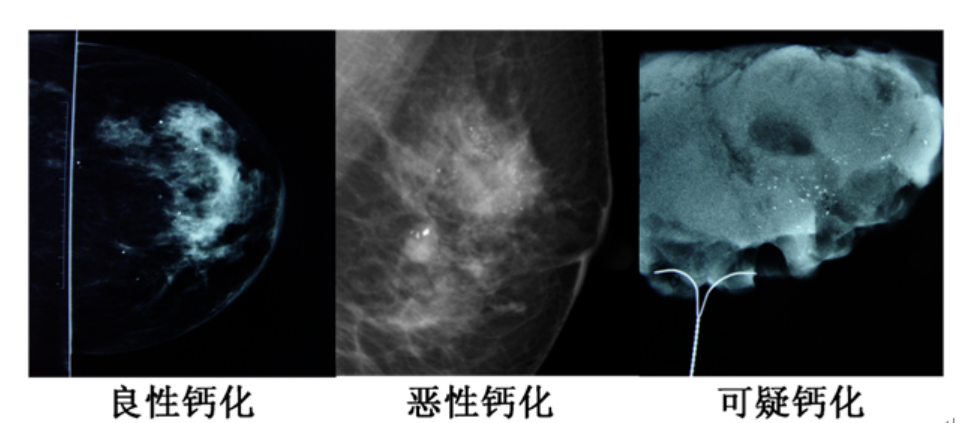

鈣化灶在鉬靶報告上表現(xiàn)為片子上透亮的“白點(diǎn)”。

良性鈣化灶,“白點(diǎn)”較粗大,比較分散。

惡性鈣化灶,“白點(diǎn)”顆粒小,呈細(xì)沙樣聚集。

還有一些可疑鈣化爐,不能直接從鉬靶上判斷,需要進(jìn)一步檢查,甚至活檢明確。